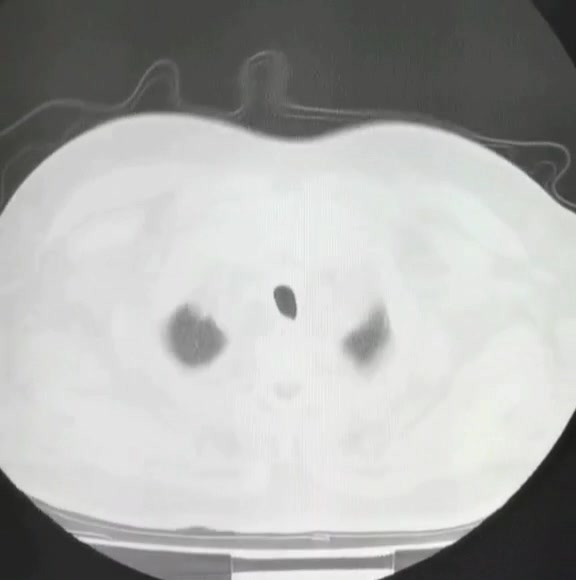

患者糖尿病肾病10年,3年前眼底手术史,2年前血肌酐300umol/L,半年前血肌酐600umol/L,还好同意建立了AVF,双下肢水肿、活动后气促2月余,听信谗言,一旦透析了,永远停不下来了,还喝那么多的水,腿肿的硬邦邦的,如同摸篮球一般,今日找到我,居然说腿不肿?无知啊,肿的按不动!说话都带喘的,走2m,都吩吩的!急症入院,半卧位,心电监护,血氧饱和度仅有86%,血气分析提示I型呼吸衰竭!真是不作死就不会死啊!

血气分析:符合I型呼吸衰竭